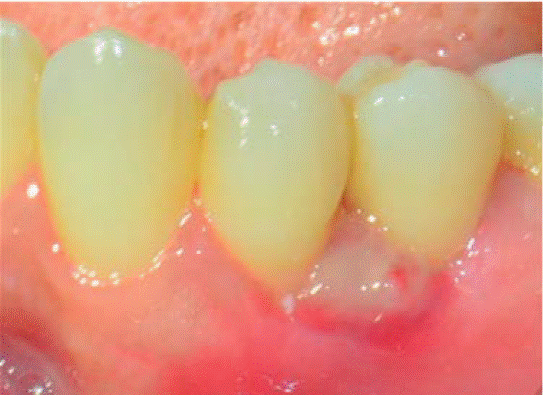

Controles: después de una semana se observó reducción del volumen de la lesión, sin embargo, persistía la coloración rojiza en la zona, por lo cual se mantuvo en observación (Figura 7). A las dos semanas se observa ligero aumento de volumen con coloración blanquecina y rojiza, por lo que se sospecha de posible recidiva, pero a la tercera semana se apreció disminución de volumen del tejido, sin presencia de signos inflamatorios.

Durante un seguimiento de siete meses se mantuvo un adecuado nivel de higiene oral y no se presentó recurréncia de la lesión (Figura 8).

Controles: después de una semana se observó reducción del volumen de la lesión, sin embargo, persistía la coloración rojiza en la zona, por lo cual se mantuvo en observación. Después de seis meses presenta recurréncia de menor intensidad (7x7 mm) (Figura 15). Además se observa presencia de placa obteniéndose un índice de higiene oral (O'Leary) del 52%. Se realiza nuevamente una sesión de instrucción de higiene oral, remoción de placa y por segunda vez la escisión de la lesión. En esta intervención se eliminó mayor margen de tejido aparentemente sano, llegando a remover el periostio adyacente a la lesión.

Durante los siguientes controles la evolución fue favorable, manteniendo mejores niveles de higiene oral y sin presentar recurréncia de la lesión hasta un periodo de seguimiento de siete meses (Figura 16).

Controles: a la semana se observó reducción del estado inflamatorio de zona de herida (Figura 20). Durante los siguientes controles la evolución fue favorable, manteniendo mejores niveles de higiene oral y sin presentar recurrncia de la lesión hasta un periodo de seguimiento de seis meses.

Controles: después de una semana se observó coloración rojiza en la zona compatible con el proceso de cicatrización. La evolución fue favorable, manteniendo mejores niveles de higiene oral y sin presentar recurréncia de la lesión hasta un periodo de seguimiento de seis meses.

Controles: después de una semana se observó buena evolución y herida en proceso de cicatrización. Después de cinco meses no se ha presentado recurrencia de la lesión.